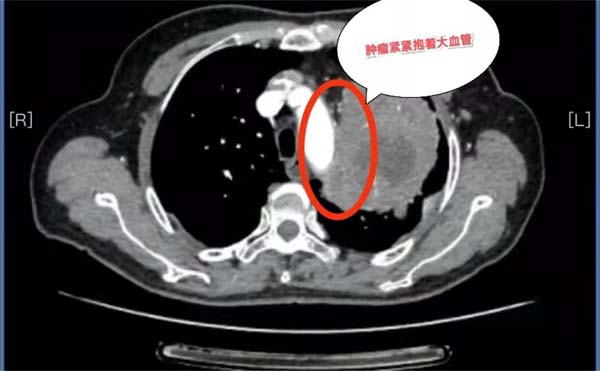

69岁的杨女士在当地医院不幸确诊为局部晚期肺癌,胸部CT检查发现左肺巨大肿瘤,已经侵犯到左肺门、左肺动脉干根部、纵隔及胸壁。当地医院建议杨女士到北京的大医院治疗。此时,患者一家陷入了极度的恐惧与绝望之中。

历经波折后求医无果,经多方打探,抱着最后一线希望杨女士和家人来到应急总医院胸外科求诊。胸外科副主任杨龙海博士从事胸外科专业多年,在肺癌方面具有丰富的诊治经验。杨龙海博士凭借丰富的临床经验,结合外院检查结果,排除远处转移,判断患者有手术的机会,且肺癌根治性手术远期效果相对较好,有治愈的可能。然而,肿瘤发现时已局部晚期,肿块巨大,侵犯到了左肺门大血管,侵犯纵隔及胸壁,加上患者伴有20多年的支气管扩张病史,致使患者症状较重,活动后气喘。这些因素导致手术需要切除整个左肺,手术难度及风险极高,切除过程会遇到肿瘤与肺门、纵隔、心包、胸膜等分离困难的难题,如果处理不当,可能出现大出血、循环呼吸衰竭等严重情况,随时危及生命。